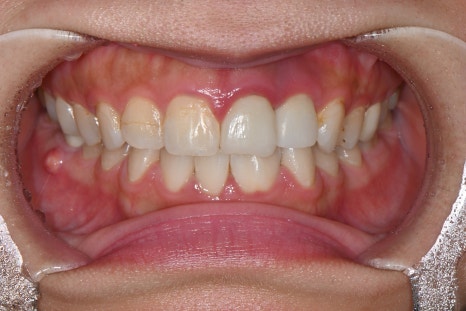

오른쪽 사진: “기존 보철물은 치아마다 색이 다르고 형태가 일정하지 않아, 앞니 라인이 울퉁불퉁하고 자연스럽지 않아 보였습니다.”